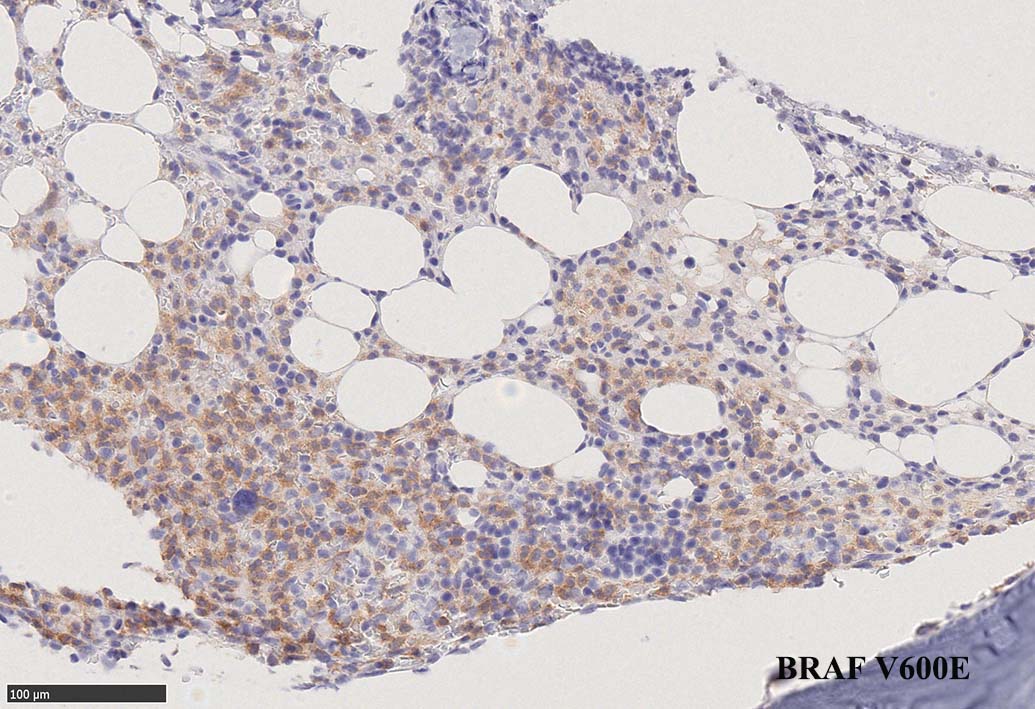

BRAF V600E変異タンパクの免疫染色(山梨医大 大石先生に染色していただきました. ベンタナ, Optiview)

Pathological Diagnosis: Hariy cell leukaemia